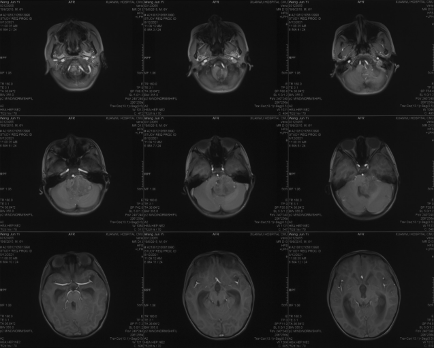

Preoperative CT

Preoperative enhanced MRI